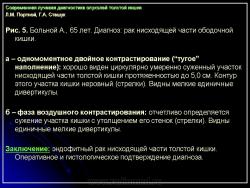

1) утолщение стенки, неровность контура и сужение просвета одного из участков кишки (рис. 5);

2) сохранение на расправленной от естественной складчатости поверхности слизистой кишки небольшого участка бариевой взвеси (типа звездочки или другой конфигурации) диаметром от 0,5 до 1,5 см – симптом ранних признаков опухоли (рис. 6);